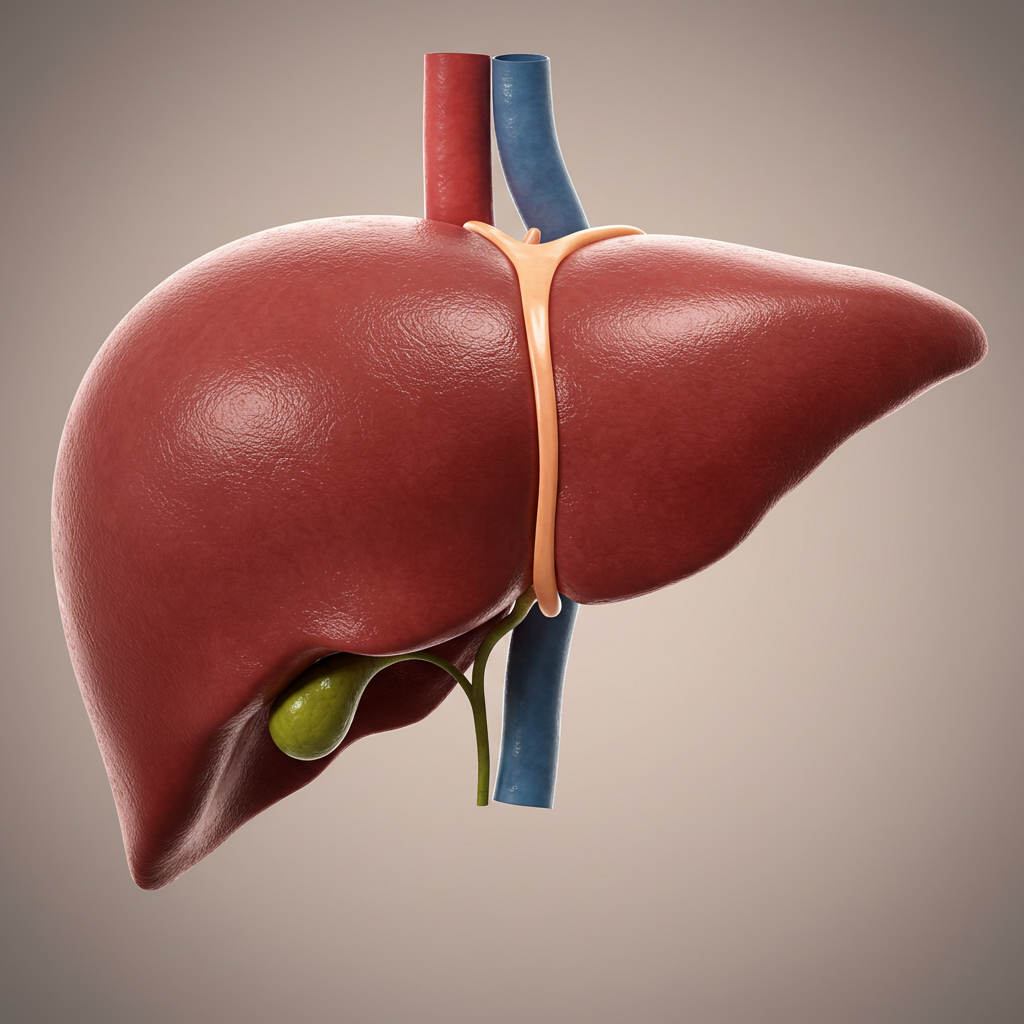

Ele é capaz de tratar completamente as principais doenças que podem atingir seu fígado, a (DHGA) Doença Hepática Gordurosa Alcóolica, (DHNGA) Doença Hepática Gordurosa não Alcóolica.

O acúmulo de gordura no fígado está diretamente ligado aos hábitos do dia a dia e à sobrecarga metabólica do organismo, podendo causar:

- Auxilia no suporte à função hepática e ao metabolismo de gorduras

- Auxilia no suporte à função hepática e no metabolismo de gorduras

- Apoia o equilíbrio metabólico e a saúde do fígado

Ajuda a restaurar a função hepática, recuperar níveis de energia da juventude e derreter anos de gordura abdominal!

Figdetox age restaurando as celulas do Fígado, fazendo com que seu figado volte a funcionar normal, eliminando a gordura e se auto regenerando.